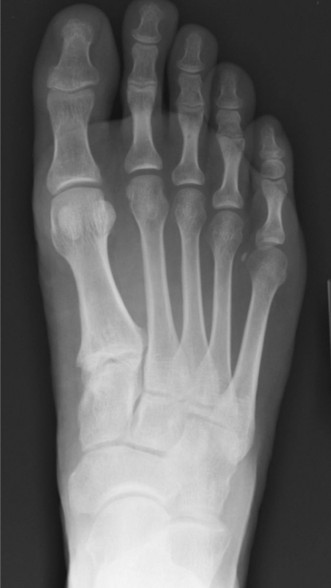

A 27-year-old, competitive triathlete sustained an injury to her left foot while trail running when she had a…